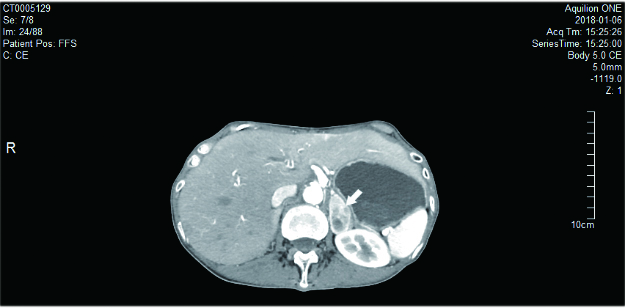

1 资料与方法患者1,女,22岁,因“发现肾上腺占位10 d”入住我院泌尿外科,无头痛、心悸、大汗,无高血压、低血钾,无满月脸、水牛背、皮肤紫纹,无月经紊乱等不适。完善皮质醇节律及醛固酮肾素比值后未见明显异常,尿香草扁桃酸(vanillylmandelic acid, VMA):26.20(0.1-68.6)μmol/24 h。肾上腺增强MRI:右侧肾上腺区域见类圆形等T1长T2异常信号影,大小约29 mm×37 mm,嗜铬细胞瘤可能性大(图 1A)。增强CT:右侧肾上腺见肿块影,大小约38 mm×29 mm,嗜铬细胞瘤可能(图 1B)。全麻下行腹腔镜下右肾上腺肿瘤切除术,手术过程顺利,术中血压心率平稳。手术病理:(右肾上腺)嗜铬细胞瘤。术后患者无明显不适,血压平稳,出院后未予特殊治疗。术后20天患者出现头痛,伴头晕、恶心呕吐,四肢抽搐2次,抽搐时伴双眼上视,至我院急诊就诊。查体:体温37.7℃,脉搏140次/min,血压205/148 mmHg,心律齐,双下肢无水种。辅助检查:血甲氧基去甲肾上腺素:111.3(< 112) pg/mL,血甲氧基肾上腺素:54.8 (< 61)pg/mL,尿VMA:56.20(0.1-68.6)μmol/24 h。心电图:窦性心动过速,下壁异常Q波伴ST段抬高改变,前侧壁、高侧壁ST段压低。头颅MRI:两侧枕顶叶及部分额叶皮质、左侧尾状核头肿胀伴信号异常,考虑可复性后部性脑白质病综合征可能。间碘苄胍(metaiodobenzylguanidine, MIBG)显像:肾上腺髓质显像未见明显异常。入院后予乌拉地尔、硝酸甘油静脉维持控制血压,血压稳定后逐渐减量,加用多沙唑嗪、厄贝沙坦。1周后患者症状缓解,血压平稳,复查头颅MRI未见明显异常。出院后继续口服多沙唑嗪、厄贝沙坦治疗。半年后逐渐停药,血压监测平稳。

图 1 肾上腺增强MRI:右侧肾上腺区域见类圆形等T1长T2异常信号影,大小约29 mm×37 mm,内部信号欠均匀,边缘光整,下腔静脉受压前移,增强后病灶明显持续性强化,嗜铬细胞瘤可能性大(箭头)。 B:肾上腺增强CT:右侧肾上腺见肿块影,大小约38 mm×29mm,内部密度不均,增强扫描呈明显不均匀强化,边界尚清,下腔静脉受压前移,嗜铬细胞瘤可能(箭头) |